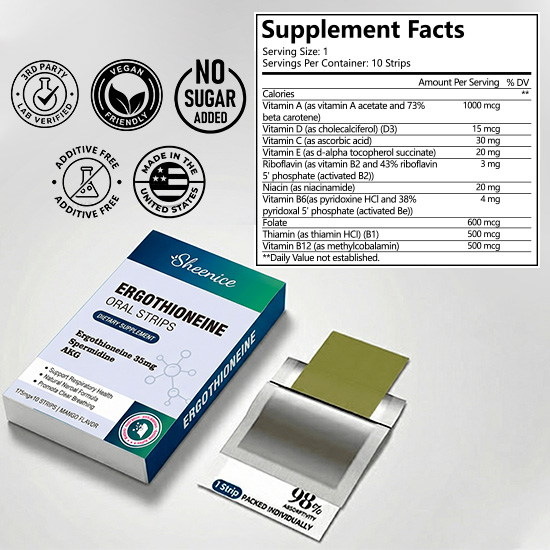

This product contains over 20 carefully selected herbs and natural nutrients, designed to help support lung health, promote smoother breathing, and enhance overall respiratory comfort.